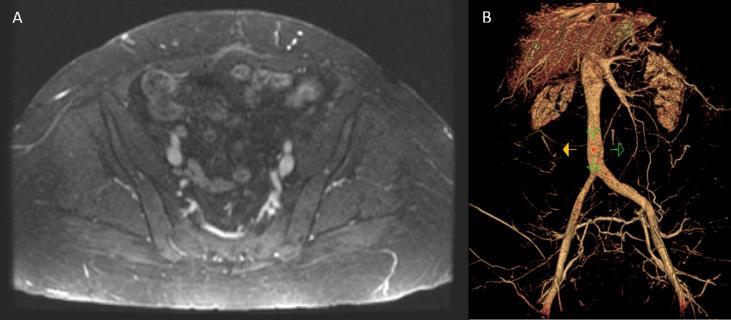

Multidisciplinary management of extensive intravenous leiomyomatosis: A coordinated effort of a single institution.

https://cdn.ncbi.nlm.nih.gov/pmc/blobs/b2f0/7114892/8c0238adb0bd/gr1.jpg